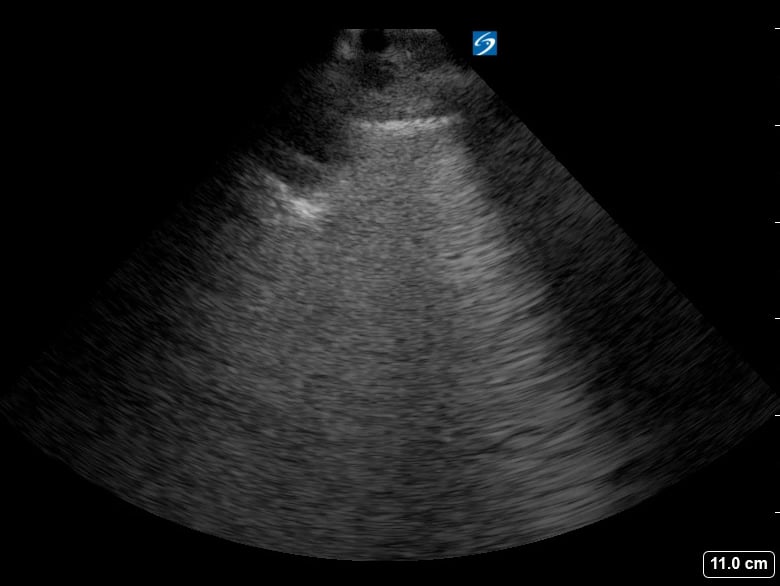

Lung consolidation in medical ultrasound refers to the solidification of lung tissue due to the accumulation of fluid, cells, or other substances, replacing the air within the alveoli. This pathological change commonly indicates conditions like pneumonia or atelectasis. On ultrasound, consolidated lung appears hyperechoic (bright) with a tissue-like echotexture, often resembling the liver (hepatization).

Identifying lung consolidation via ultrasound is crucial for rapid diagnosis and management in acute care settings. This non-invasive imaging technique allows clinicians to visualize air bronchograms (air-filled bronchi within consolidated tissue) and pleural effusions, aiding in differentiation from other lung pathologies. Ultrasound offers a portable and radiation-free alternative for bedside assessment of lung parenchyma, optimizing patient care.